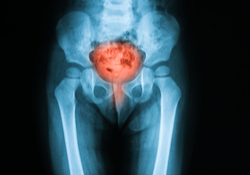

Qu'est-ce que c'est une cystite ou inflammation de la vessie?

La vessie est le réservoir des urines et se trouve dans le bas du ventre. Les urines sont évacuées à l'extérieur par l'urètre. Lors d'une inflammation de la vessie, la paroi interne de la vessie est enflammée, parfois même l'urètre.